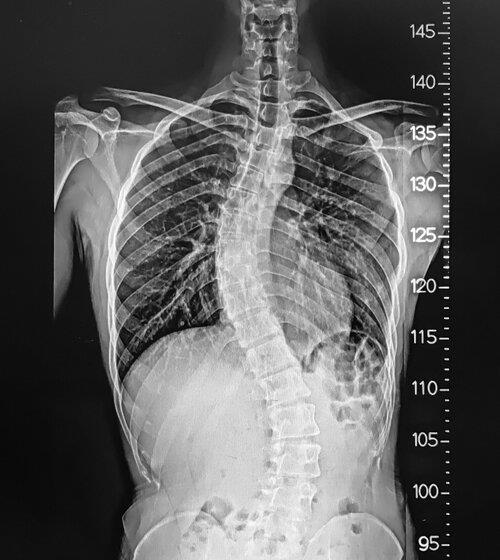

In Arizona, Back fusion is a surgical procedure that involves joining two or more vertebrae in the spine together. This surgery is used to treat conditions such as degenerative disc disease, scoliosis, and spinal fractures. The goal of Dr. Andrew Chung is to reduce pain and increase stability in the spine, allowing his patients to return to normal activities within a few days of the surgery. He is highly skilled in performing surgical procedures and utilizes advanced techniques and medical technology. Before undergoing this latest surgical treatment, it is essential to consult with your surgeon. For more information, please visit the website.

Dr. Andrew Chung provides Back Fusion treatment in Surprise using the latest robotic techniques to join two or more bones in the spine. At the Banner Health Clinic, he can help to recover spine health with physical therapy. The latest spine surgical procedure is necessary when patients have degenerative disc disease, scoliosis, and other spine issues. As a dual fellowship medical professional, he knows how to use small incisions during surgical procedures.